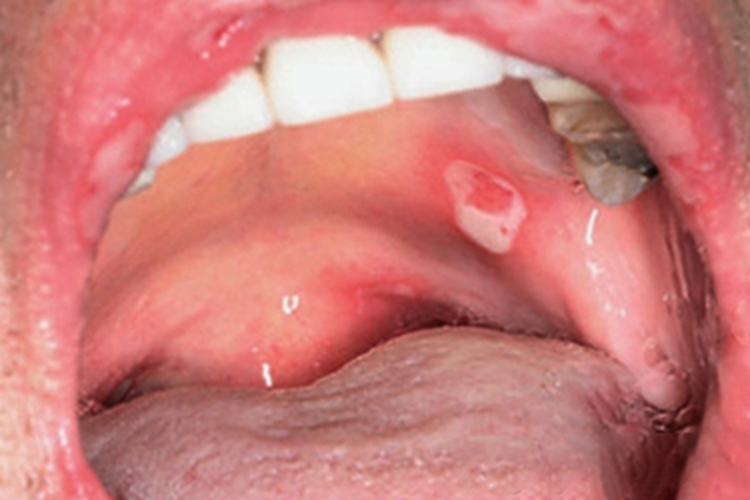

副肿瘤性天疱疮可见患者口腔出现白色溃疡,周围绕以红晕,可伴有糜烂、裂口,裂口处颜色鲜红,边缘微微泛白,患者会有明显痛感,影响进食喝水。